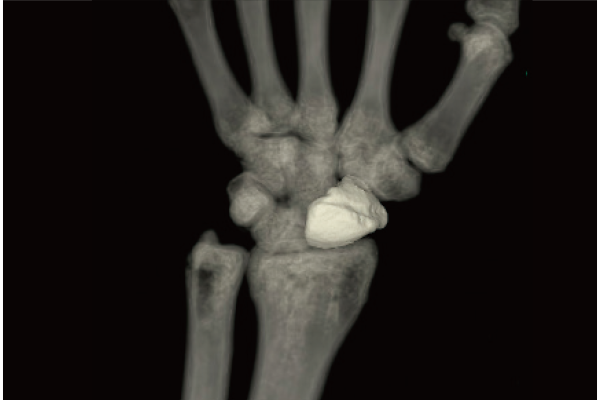

One-click operation to extract the areas that touch bones.

Bones are extracted or removed with one click based on the CT value and the shape of the region of interest recognized by REiLI technology.

Carpal bones removal